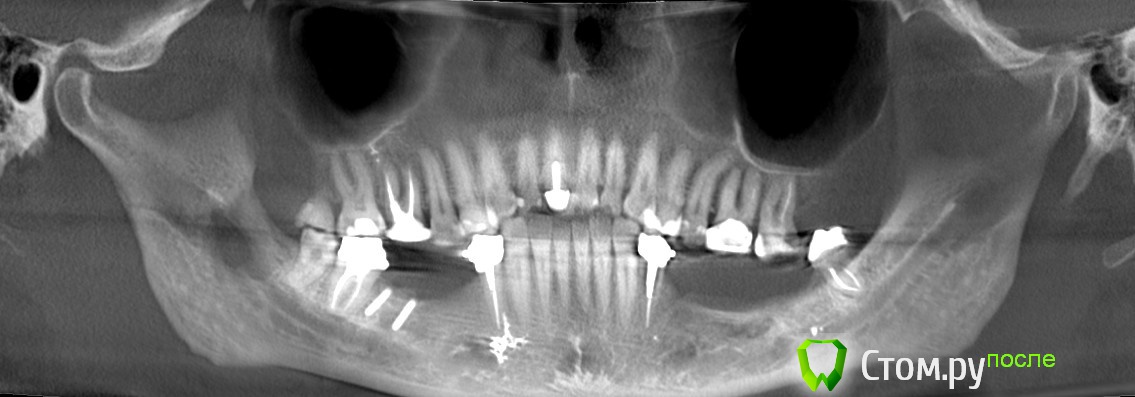

Марьяна Опубликовано 22 ноября, 2014 Поделиться Опубликовано 22 ноября, 2014 (изменено) Уважаемые врачи. У меня возникло некое недопонимание с достаточно уважаемым коллегой.По данным КТ я вижу двойной перелом ветви челюсти. Он мне говорит, что это артефакты. И советует сделать спиральную томографию и для него КЛКТ не информативна.Прилагаю 3D реформат, до и спустя 4 месяца после операции аугментации с забором костного блока ретромолярно на нижней челюсти справа. Сразу отмечу- это моё КТ. Пациентом являюсь я сама.Если необходимо будет, вышлю дайкомы. Первый файл до операции. Остальные после. Первые два - программа EZ-Vision. Если понизить плотность костной ткани(в программе естественно), то будет видно, что был так же перелом в области угла. Два файла последних - программа Invivo5(Анатомаж).Нужны ваши мнения. Изменено 22 ноября, 2014 пользователем Марьяна Ссылка на комментарий

Марьяна Опубликовано 22 ноября, 2014 Автор Поделиться Опубликовано 22 ноября, 2014 Попробую. В программе конечно проще поймать линии переломов.Ну вот ..в области конкретно ветви: Ссылка на комментарий

Марьяна Опубликовано 22 ноября, 2014 Автор Поделиться Опубликовано 22 ноября, 2014 В области угла зигзагообразная линия ..практически уже не визуализируется: Ссылка на комментарий

kriokov Опубликовано 23 ноября, 2014 Поделиться Опубликовано 23 ноября, 2014 похоже на перелом я бы не стал с выводами торопиться,К ТопикстартеруЕсли не затруднит, сделайте из кт панораму (оптг, это возможно сделать почти в любой программе просмотрщике , которая есть на диске), одну до забора блока, вторую после установки блока , и залейте обе. Мне кажется обычные панорамные снимки будут более информативны, особенно в ситуации после забора и трансплантации блока. имхо 2 Ссылка на комментарий

Марьяна Опубликовано 23 ноября, 2014 Автор Поделиться Опубликовано 23 ноября, 2014 (изменено) я бы не стал с выводами торопиться,К ТопикстартеруЕсли не затруднит, сделайте из кт панораму (оптг, это возможно сделать почти в любой программе просмотрщике , которая есть на диске), одну до забора блока, вторую после установки блока , и залейте обе. Мне кажется обычные панорамные снимки будут более информативны, особенно в ситуации после забора и трансплантации блока. имхо Хорошо, вот:Позже закину ссылку на дайкомы. Изменено 23 ноября, 2014 пользователем Марьяна Ссылка на комментарий

kriokov Опубликовано 23 ноября, 2014 Поделиться Опубликовано 23 ноября, 2014 Хорошо, вот: Марьяна Александровна, по панораме.Мне кажется нет перелома нижней челюсти в обл угла и в обл ветви. Но это мое личное мнение и я его попытаюсь обосновать.Зеленая стрелка показывает на место забора блокажелтая на линию восходящей части венечного отростка-- там нет непрерывностисиняя стрелка -- ветвь, линия может быть и артефактом связанным с забором блока, если он был значительным по протяжению.Мне кажется , Вам надо списываться с доктором, ( напомнить ему , что Вы стоматолог, еще раз без обиняков изложить все вопросы которые Вас тревожат), осмотр, и решать , что дальше делать. http://www.imageup.ru/img214/1954483/maryana.jpg Ссылка на комментарий